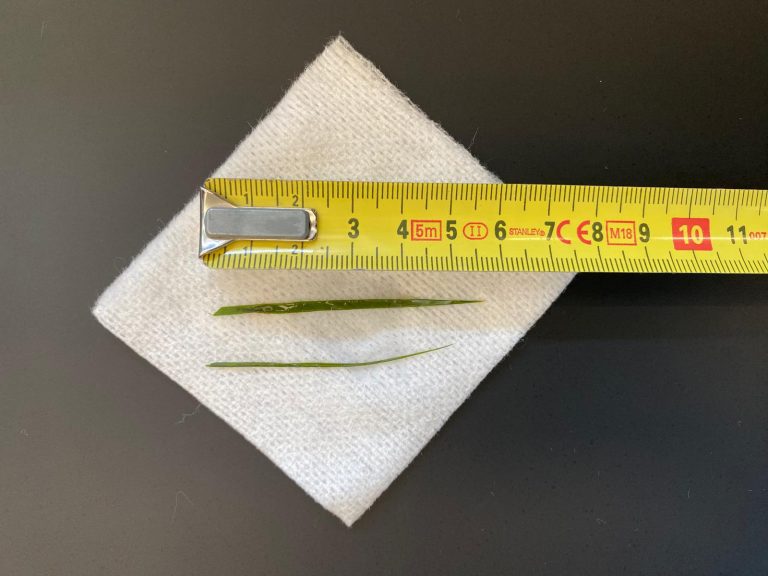

En dit bleek inderdaad het geval. In september van 2016 constateerde we, met behulp van een echo, weer nieuwe blaassteentjes bij Amy.

Ze waren nog wel heel klein, maar ze waren er wel weer. Ondertussen had onze dierenartspraktijk geïnvesteerd in allerlei scopen.